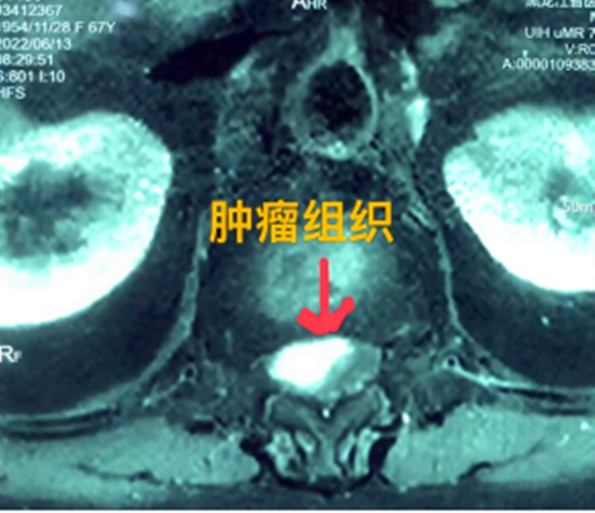

四公分大脊髓腫瘤充滿(mǎn)髓腔完全壓迫神經(jīng)

黑龍江經(jīng)濟(jì)網(wǎng)訊(林穎 董宇翔 梁新立) 近日,黑龍江省醫(yī)院收治了一名胸椎管內(nèi)腫瘤患者,該患者為少見(jiàn)的脊髓腫瘤,腫瘤長(zhǎng)度達(dá)到四公分,充滿(mǎn)髓腔且神經(jīng)已經(jīng)完全受壓。最終,省醫(yī)院神經(jīng)外一科專(zhuān)家和骨外一科專(zhuān)家團(tuán)結(jié)協(xié)作,共同完成了這臺(tái)高難度腫瘤切除術(shù),患者現(xiàn)已順利康復(fù)出院。

據(jù)省醫(yī)院神經(jīng)外一科陶宇醫(yī)生介紹,家住外地的張大娘最近總感覺(jué)雙下肢疼痛、無(wú)力,且排尿困難及便秘,伴有行走困難。時(shí)間長(zhǎng)了,張大娘病情逐漸加重,劇烈的疼痛甚至讓她無(wú)法完整入睡。在當(dāng)?shù)蒯t(yī)院,張大娘按腰椎肩盤(pán)突出接受治療,但未見(jiàn)好轉(zhuǎn),隨后進(jìn)行的胸椎MRI(核磁共振)檢查,結(jié)果不禁讓張大娘和家屬瞠目結(jié)舌,原來(lái)張大娘患的竟然是少見(jiàn)的脊髓腫瘤。

張大娘住進(jìn)了黑龍江省醫(yī)院神經(jīng)外一科,該科孫國(guó)章主任醫(yī)師熱情地接待了張大娘,并邀請(qǐng)骨外一科專(zhuān)家共同為她進(jìn)行了聯(lián)合會(huì)診。發(fā)現(xiàn)張大娘病情十分復(fù)雜棘手,脊髓腫瘤體積較大,充滿(mǎn)髓腔且神經(jīng)已經(jīng)完全受壓,需要手術(shù)來(lái)完整切除。同時(shí)還發(fā)現(xiàn)張大娘的胸腰部曾受過(guò)兩次外傷,伴有多處骨折,這對(duì)接下來(lái)的手術(shù)操作帶來(lái)一定影響。